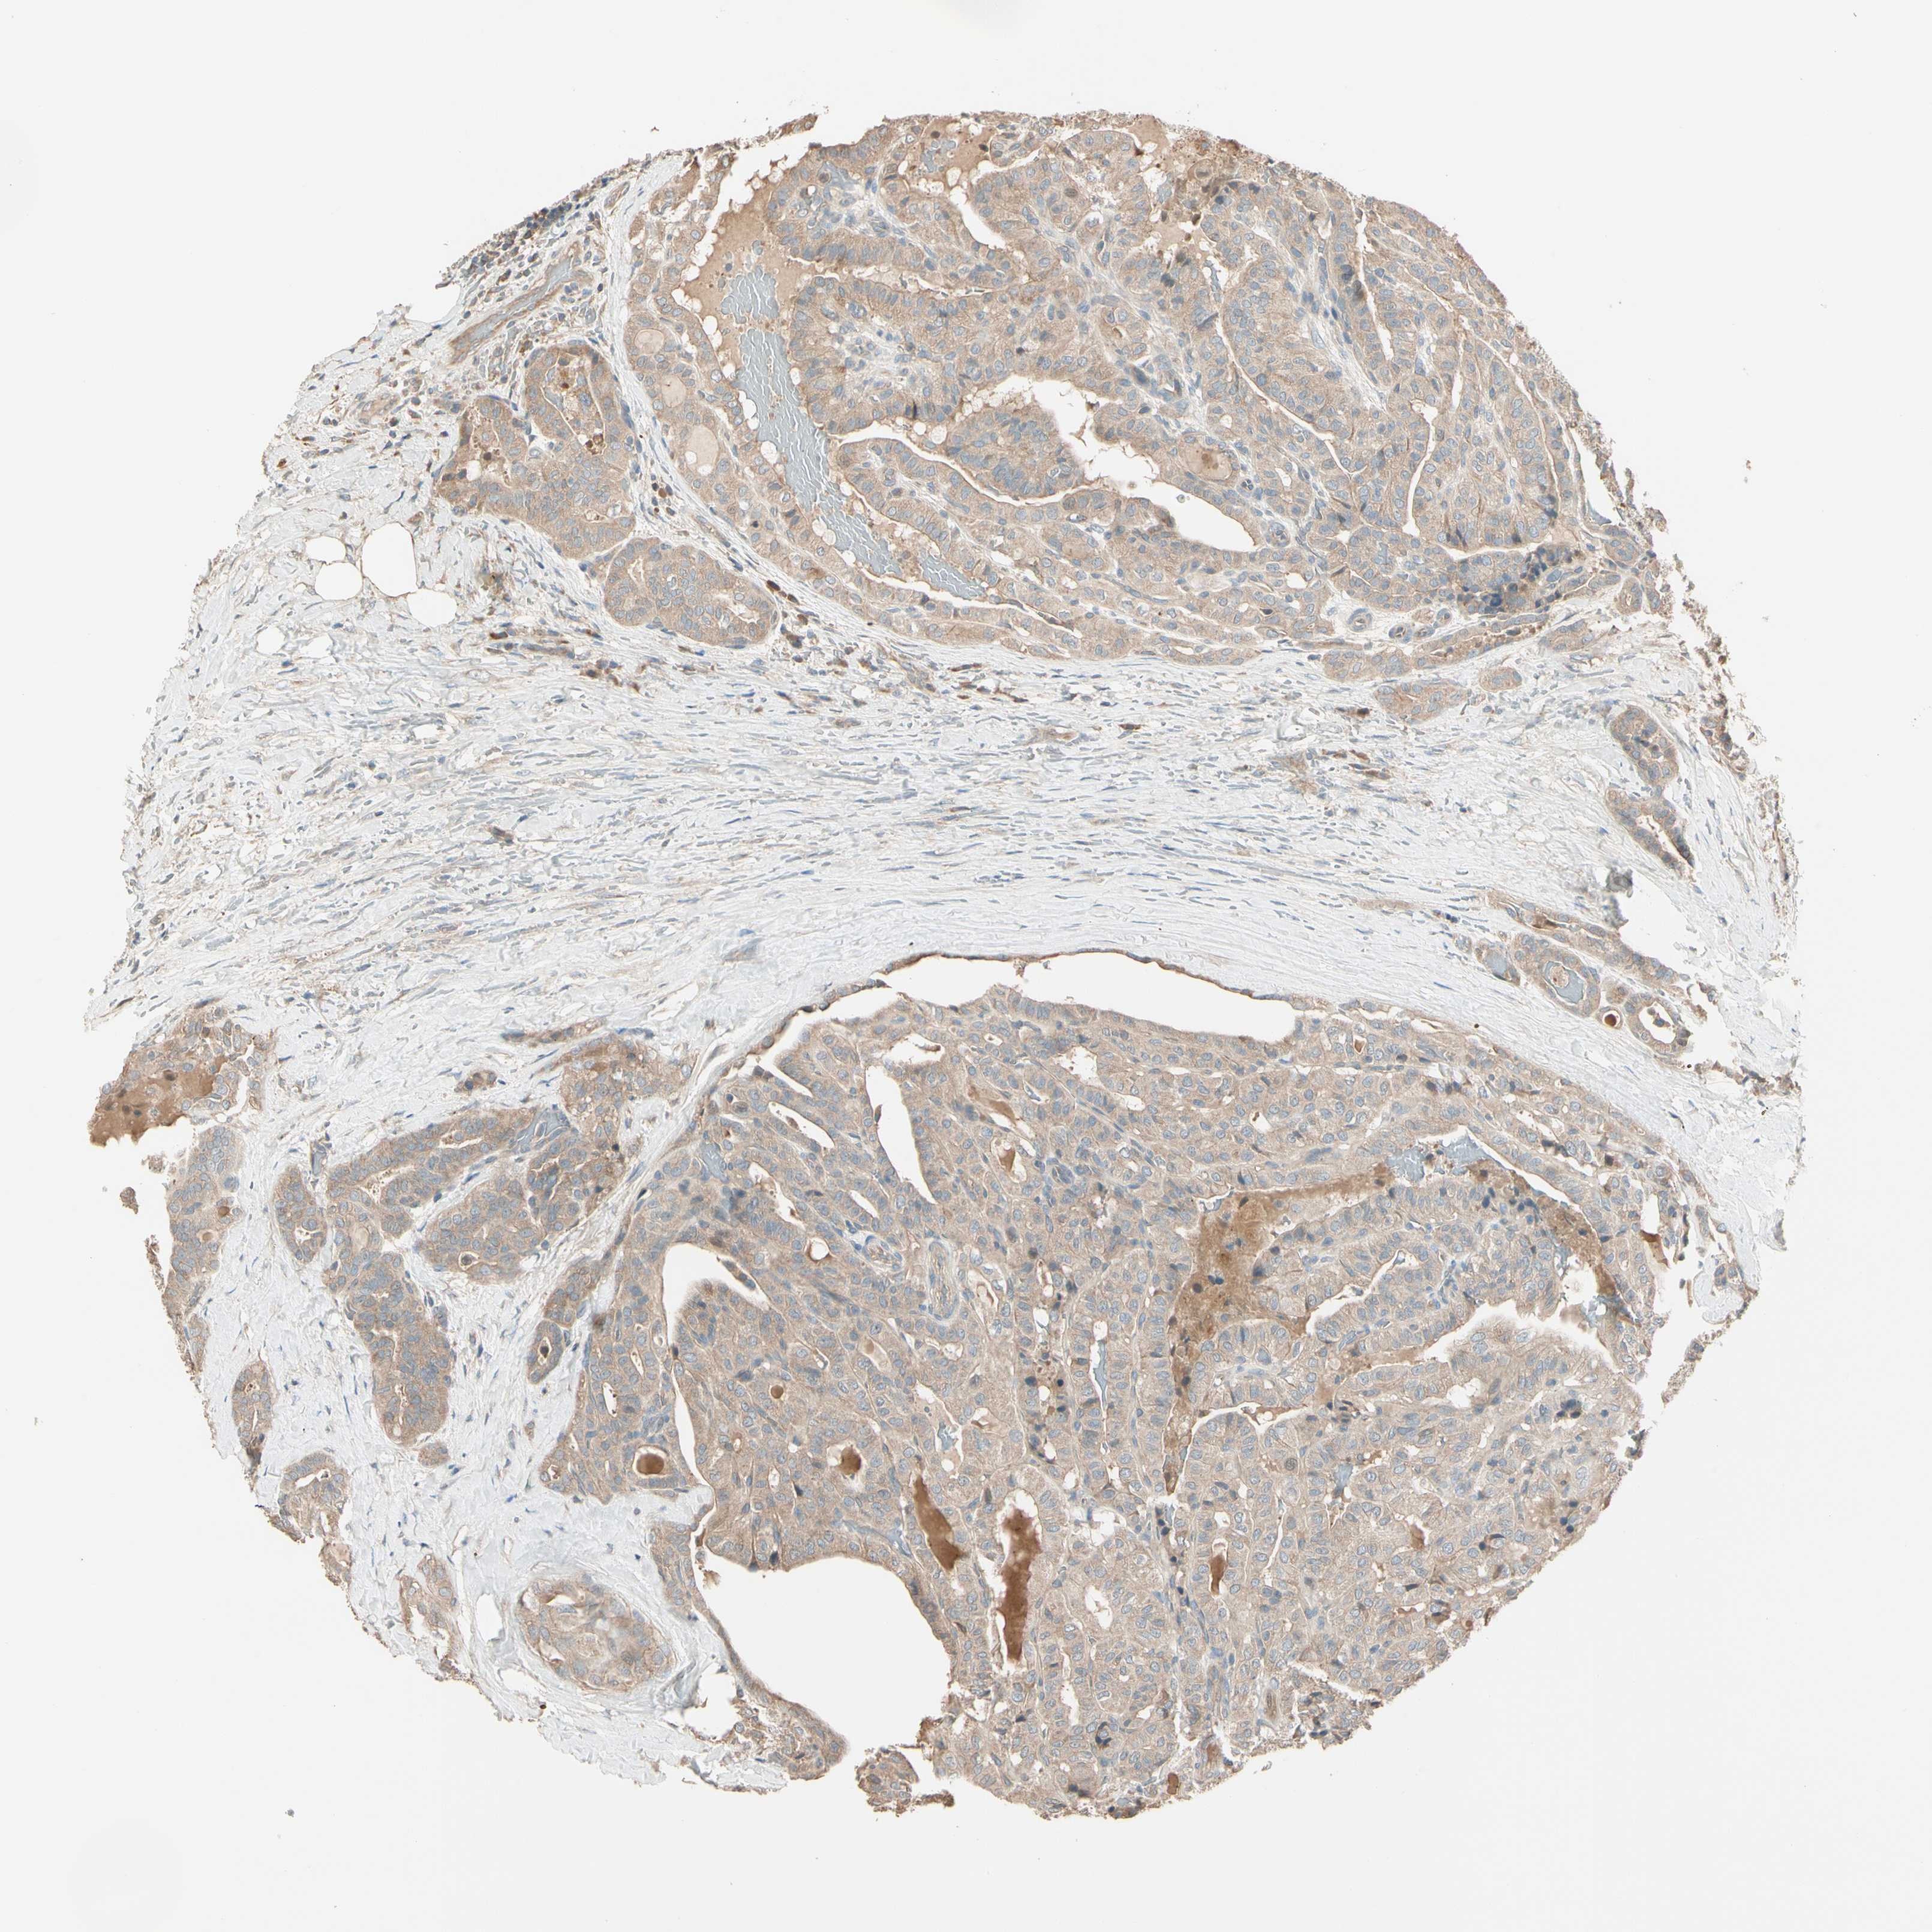

THYROID CANCER - Protein expressioni

A mouse-over function shows sample information and annotation data. Click on an image to view it in a full screen mode. Samples can be filtered based on level of antibody staining by selecting one or several of the following categories: high, medium, low and not detected. The assay and annotation is described here.

Note that samples used for immunohistochemistry by the Human Protein Atlas do not correspond to samples in the TCGA dataset.

Antibody stainingi

Antibody staining in the annotated cell types in the current human tissue is reported as not detected, low, medium, or high, based on conventional immunohistochemistry profiling in selected tissues. This score is based on the combination of the staining intensity and fraction of stained cells.

Each image is clickable and will lead to virtual microscopy that enables deeper exploration of all samples and also displays staining intensity scores, fraction scores and subcellular localization as well as patient and tissue information for each sample.

Antibody HPA006746

Antibody CAB009805

Staining

High

Medium

Low

Not detected

Intensity

Strong

Moderate

Weak

Negative

Quantity

>75%

75%-25%

<25%

None

Location

Nuclear

Cytoplasmic/membranous

Cytoplasmic/membranous,nuclear

Papillary adenocarcinoma, NOS

Follicular adenoma carcinoma, NOS